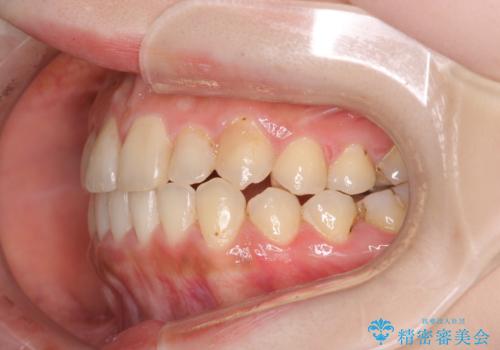

八重歯をインビザラインで非抜歯矯正

- 八重歯を主訴に来院されました。

インビザラインにて奥歯を後方に移動して八重歯が入るスペースを確保してく矯正する計画としました。

八重歯と前歯のガタガタがなくなり、歯並びがきれいになったのと、かみ合わせも改善することができました。